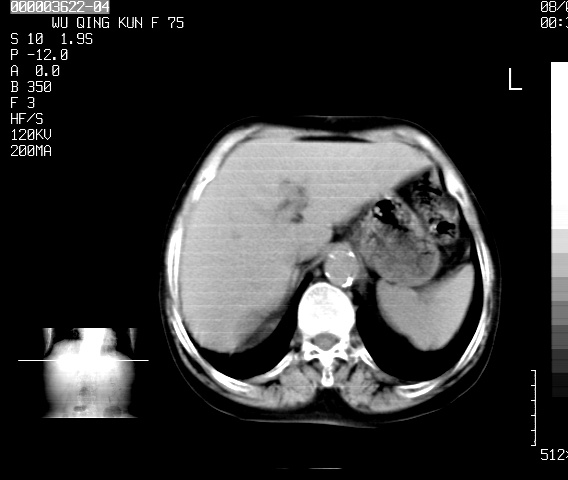

以下是引用卜一在2008-5-20 2:45:00的发言:[br]与胃腔关系密切,胃壁增厚不明显,建议行胃镜或钡餐内检查!

以下是引用dyqct在2008-5-20 10:49:00的发言:[br][quote]以下是引用卜一在2008-5-20 2:45:00的发言:[br]与胃腔关系密切,胃壁增厚不明显,建议行胃镜或钡餐内检查!